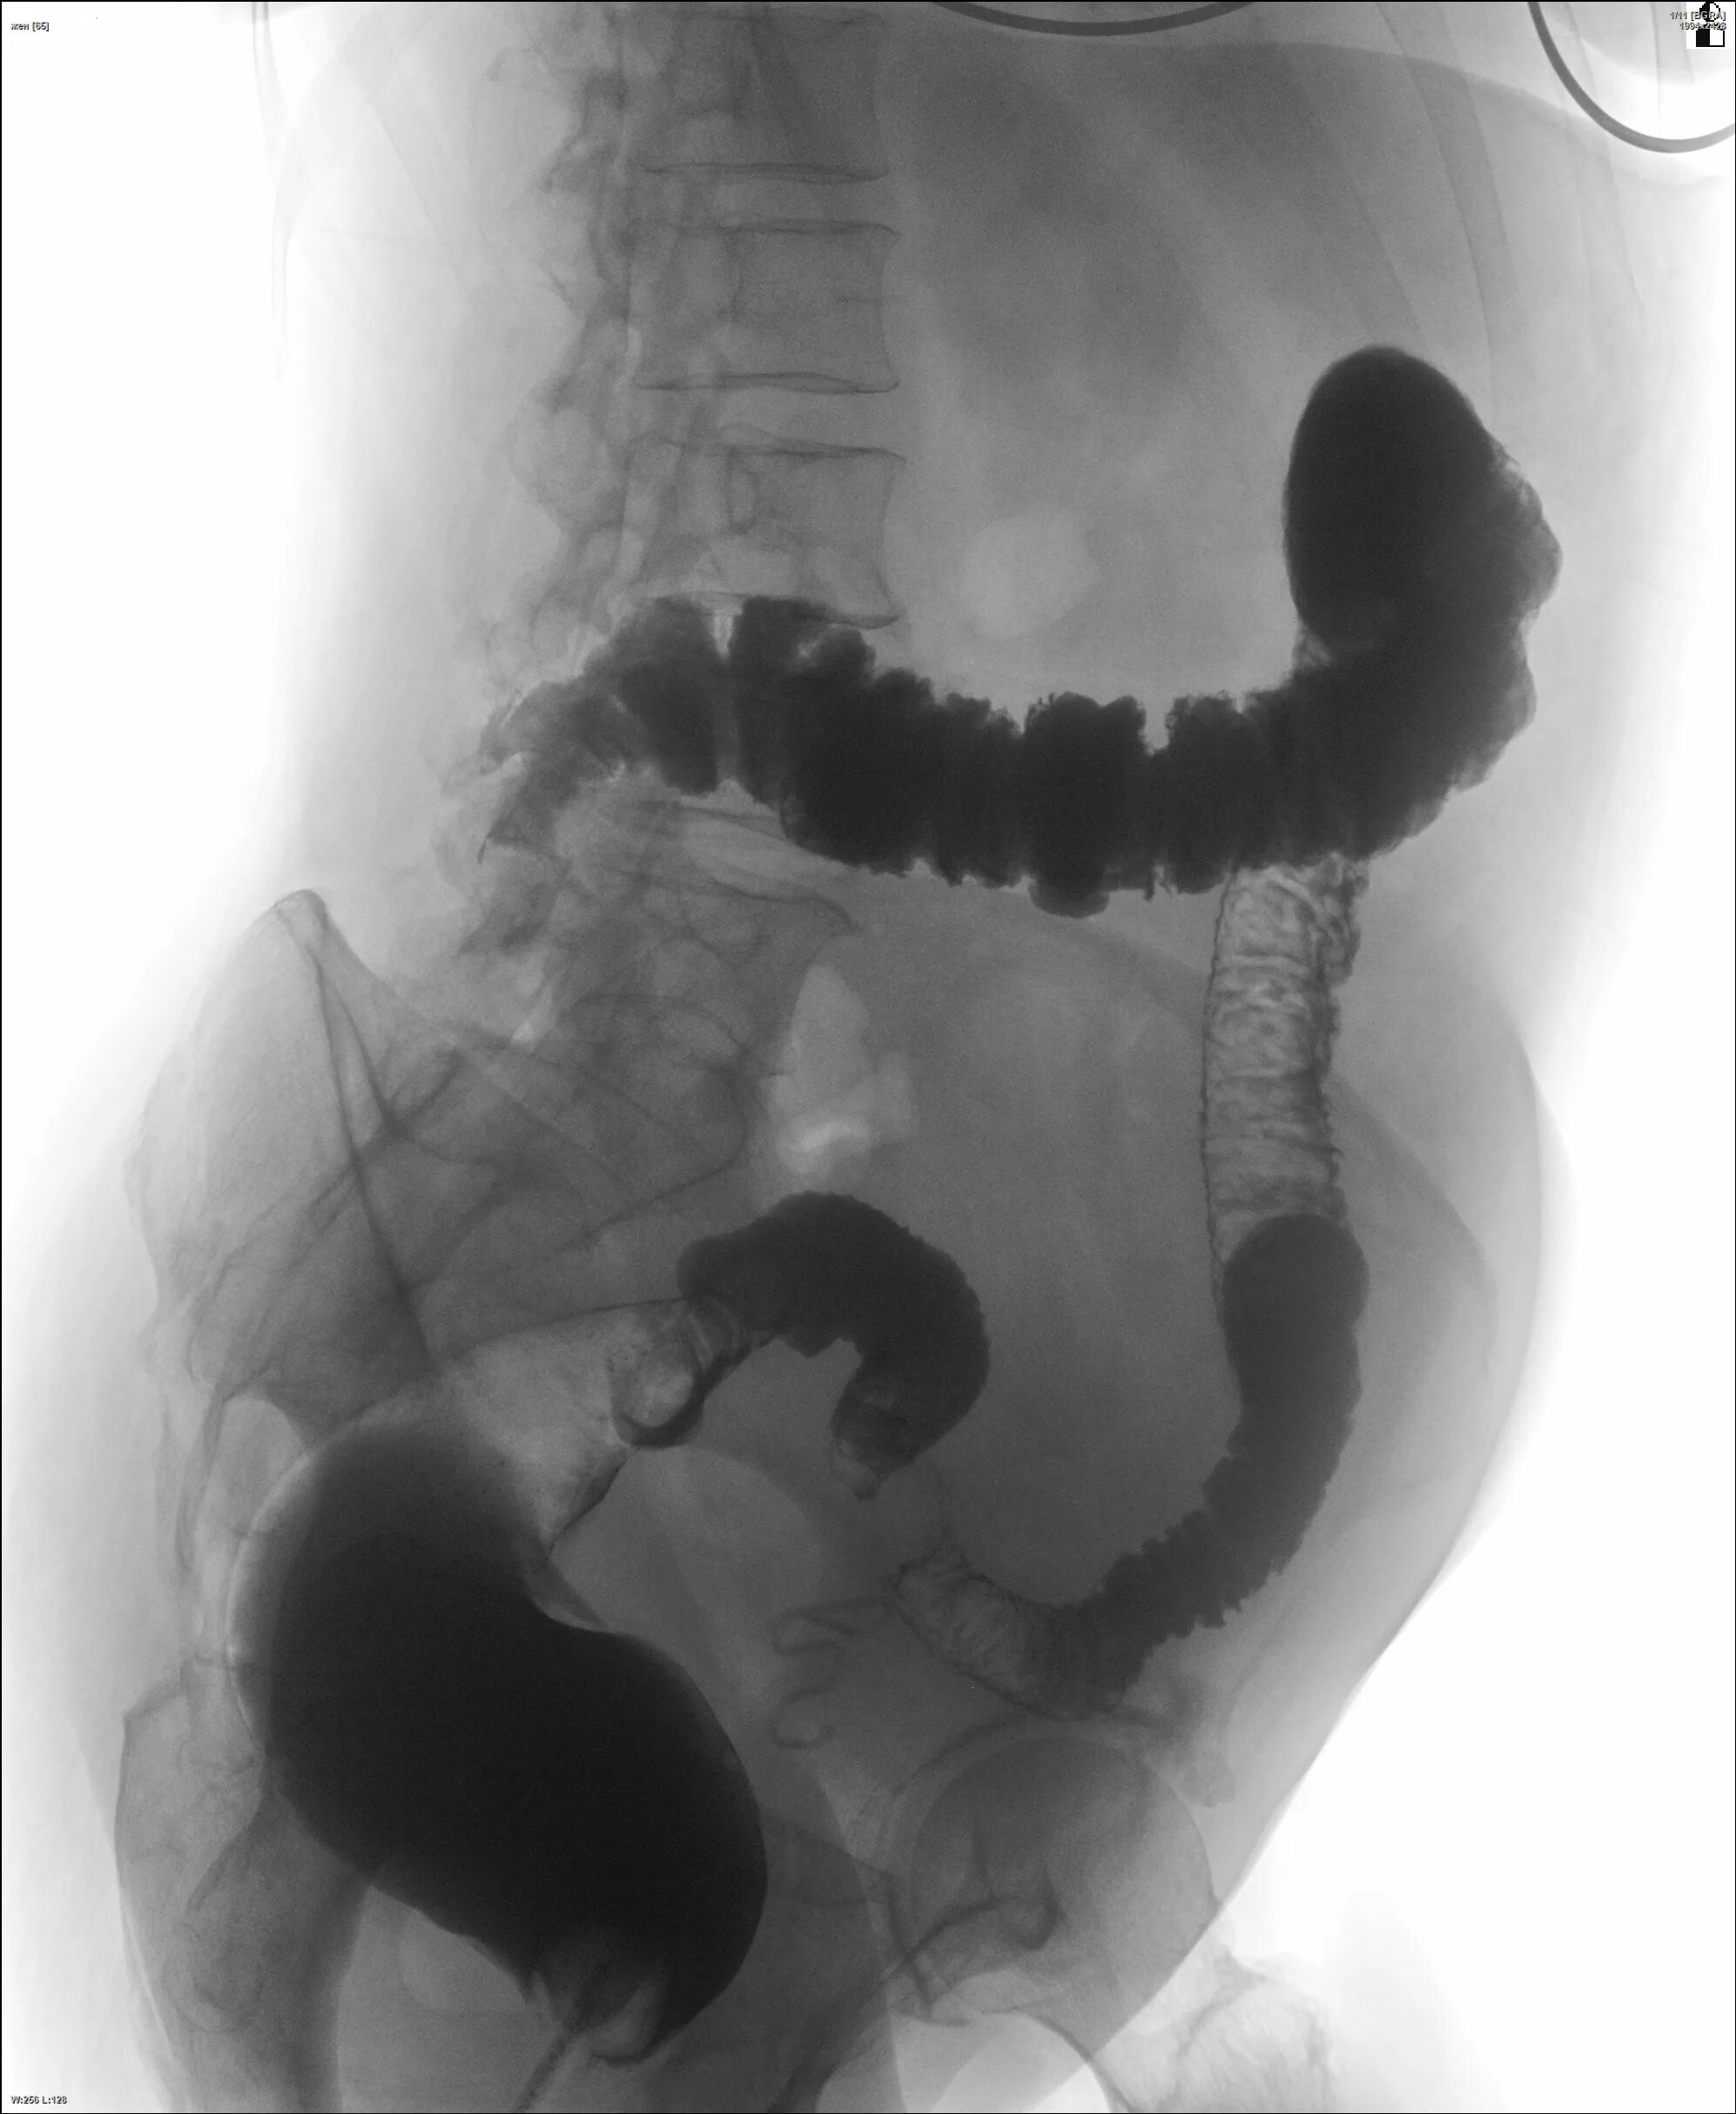

Кишечник после ирригоскопии